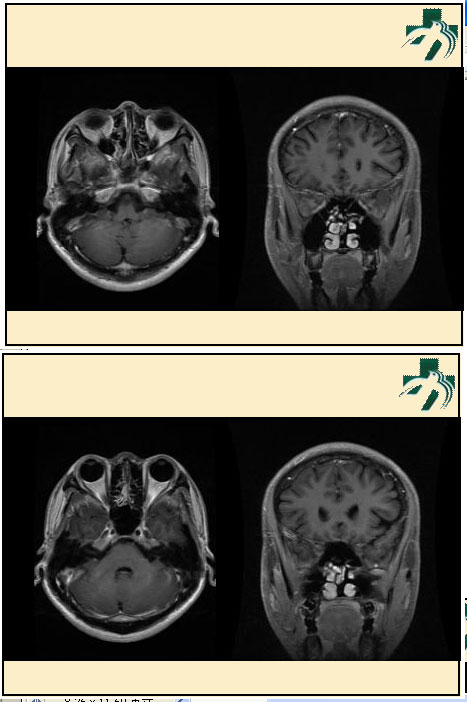

奴卡氏菌感染

第九期三博

读片会

病例之四

北京协和医院 提供

男性,22岁。自觉虫咬后皮疹、肢体麻木4月